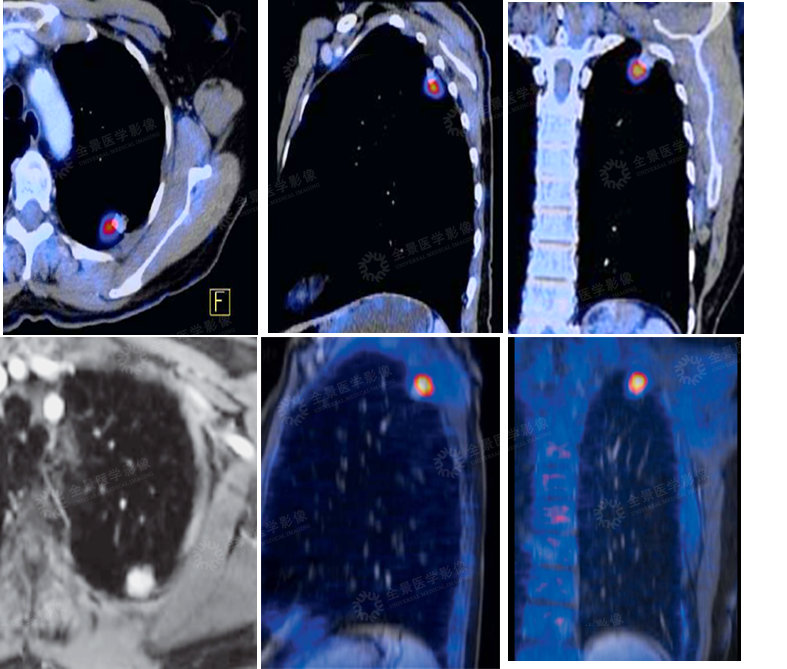

肺部

案例:中年男性,左肺上叶后段结节状高信号影,FDG局限性摄取增高。

病理:腺癌。